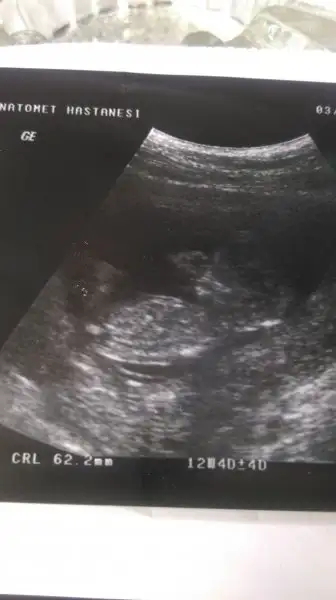

Poliklinikge gitmiştim kendi doktorum 10+6 da 20gr. Ölçmüştü ayın 15inde randevum var bakalim.

Bu doktorda iyi dedi ama haftası ile uyumlu kilosu için tombiş bile dedi şimdi aklım karıştı

ınan cok cok sevındım ,,, kanama alanları da sırasıyla bıtıyor ınsallah ... ıns. cumartesı gunu guzel hayırlı haberler alırım bende kontrolumuz var 3 lu taraama ıcın kan vereceğım

Kızlar selam. Nasılsınız ? Biz de bugün itibari ile 14+1 deyiz Allah’ın izni ile.. gebelik belirtileri, kusma vs.. bittiğinden beri ben hiç birşey hissetmiyorum. Hatta bazen hamilemiyim diye şüphe ediyorum. :) siz bebeklerinizi hissediyor musunuz? Benim ilk gebeliğim ondan nasıl hissedildiğini de bilmiyorum zaten